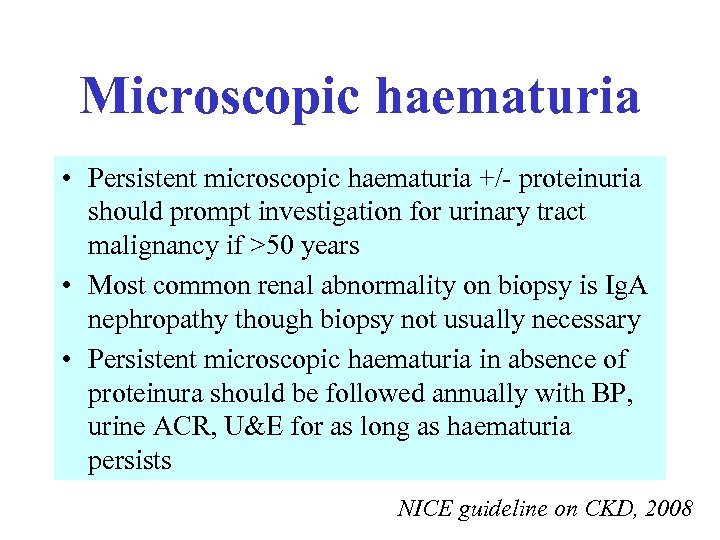

Microscopic haematuria • Persistent microscopic haematuria +/- proteinuria should prompt investigation for urinary tract malignancy if >50 years • Most common renal abnormality on biopsy is Ig. A nephropathy though biopsy not usually necessary • Persistent microscopic haematuria in absence of proteinura should be followed annually with BP, urine ACR, U&E for as long as haematuria persists NICE guideline on CKD, 2008

Microscopic haematuria • Persistent microscopic haematuria +/- proteinuria should prompt investigation for urinary tract malignancy if >50 years • Most common renal abnormality on biopsy is Ig. A nephropathy though biopsy not usually necessary • Persistent microscopic haematuria in absence of proteinura should be followed annually with BP, urine ACR, U&E for as long as haematuria persists NICE guideline on CKD, 2008